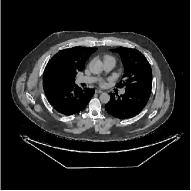

This paper was inspired by a simple observation related to our recent study [34]: for the penalized weighted-least squares (PWLS) reconstruction method using prior with a learned ST (PWLS-ST-) [34], the sparsification error histograms match a Laplace distribution over the iterations; see Fig. 1. The question then arises, “Does the learned prior experience model mismatch in testing stage?” To answer this question, we aim to investigate learned STs for regularization. This paper

The term denotes a -based sparsification error [3, 4, 5]. We expect to be more robust to sparsity model mismatch than the -based sparsification error used in [34, 36]. Fig. 1 shows histograms of sparsification error at different outer iterations of the PWLS-ST- method. Over the iterations, the sparsification error histograms appear more like a Laplace distribution than a Gaussian distribution. This observation suggests that the proposed prior model is more suitable than the prior model for PWLS-ST-based reconstruction. Section III-B1 shows that the proposed -based sparsification error term, , improves the accuracy of reconstruction compared to the prior model in [34, 36].

| views | ||||

| (a) , | (b) , | (c) , | (d) , |